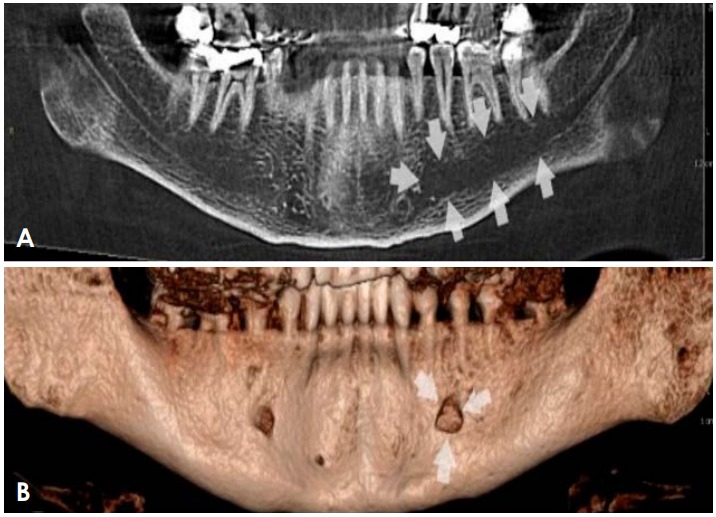

Common conditions associated with mandibular canal widening: A Iiterature review

Common conditions associated with displacement of the inferior alveolar nerve canal